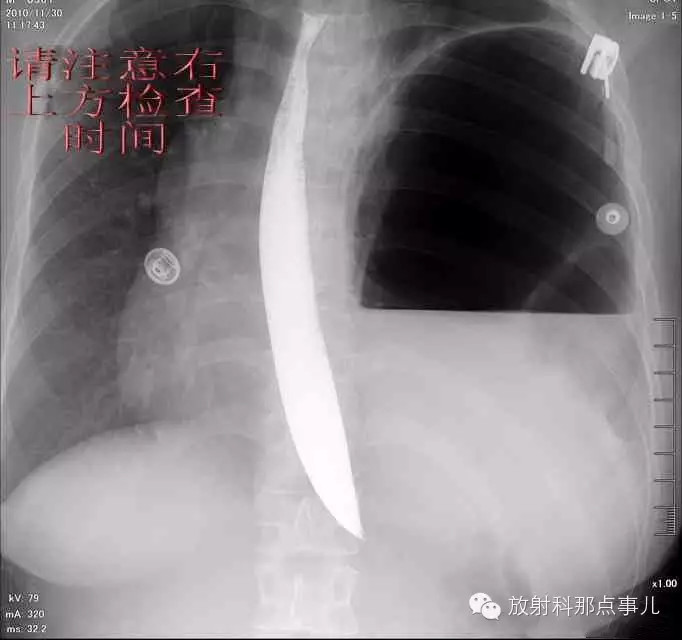

门诊腹部透视发现左侧胸腔巨大气液平面,为排除膈疝口服钡剂,但造影剂未见进入胃内。嘱住院,外科给予胃肠减压、补液等处理常规处理(未引流出明显气、液体)。5个半小时后再次检查,见少量造影剂进入消化道;为进一步了解情况,予泛影葡胺分别经胃管推注及口服,但均未进入胃内。当天进行外科急诊手术。

更正:检查时间在左上方。

大部分胃、脾及横结肠均经过胸肋三角疝入左侧胸腔内,并见疝环形成。

考虑该患者因生产过程中腹压急剧升高,导致腹内脏器经膈肌缺损或薄弱部位进入胸腔内。